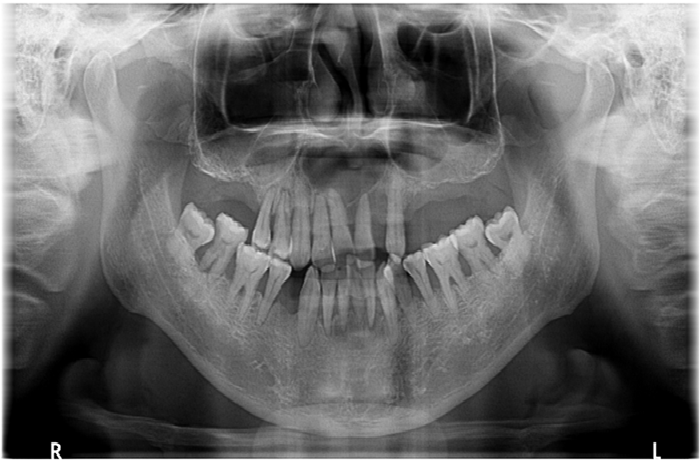

口腔全景片是通过一次X线拍摄,全面反映口腔全貌的检查方式,是一个重要的辅助检查,对牙齿种植、矫正、修复、充填和埋伏牙拔除以及肿瘤的治疗等都有很大帮助。

一般来说,口腔全景片可以看到牙齿的解剖结构、牙周状况,是否存在牙槽骨的吸收、有无龋齿的形成,可以定位埋伏牙,观察牙齿与周围的相邻关系。另外,口腔全景片也可以观察上下颌骨、上颌窦、颞下颌关节、髁突的解剖及病理情况,指导临床制定治疗方案。